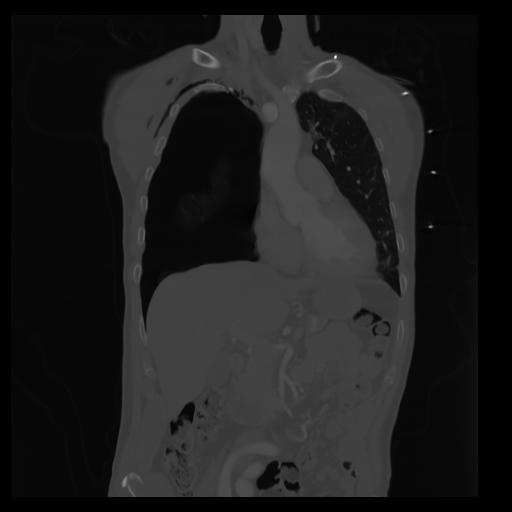

29 CUERPO,CE,Coronal,3.000,CUERPO,Coronal,